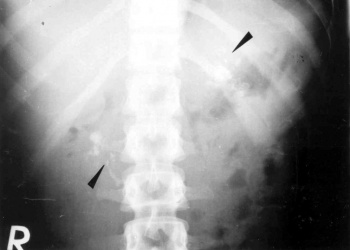

- בצילום בטן סקירה ניתן לראות ב-50% מהחולים הסתיידויות באזור הלבלב (תצלום 6.9).